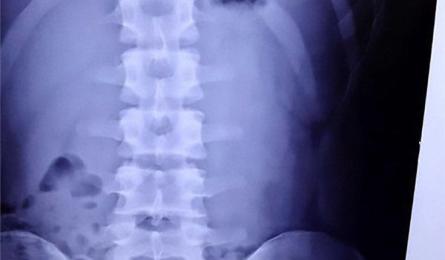

Οι πολλές ακτινογραφίες αυξάνουν τον κίνδυνο για καρκίνο των όρχεων Μια νέα αμερικανική επιστημονική έρευνα για τον καρκίνο των όρχεων έρχεται στο φως της δημοσιότητας. Σε αυτήν αναφέρεται πως η πρώιμη και... 13.11.2020 19:30